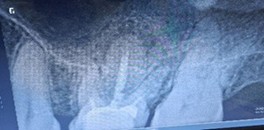

Figure 2: Immediate post-op after removing faulty restoration and access opening initiation.

Figure 2: Immediate post-op after removing faulty restoration and access opening initiation. Figure 3: Three weeks post op Xray after metapex placement revealing no marked changes in the periapical lesion.

Figure 3: Three weeks post op Xray after metapex placement revealing no marked changes in the periapical lesion.